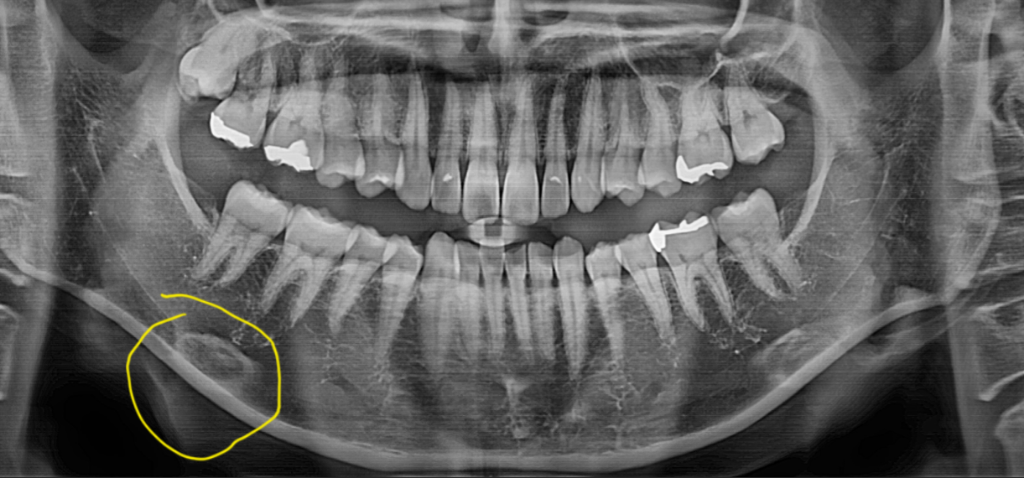

그 부위 턱뼈가 단단하거나 두께가 두꺼운 경우 이런식으로 나타납니다. 반대편도 약간 그렇습니다. 그냥두면 됩니다. 턱뼈 밑으로 지나는 신경관(하치조 신경)과 겹쳐 보이지만 정상적입니다.

해당부위의 하얀색은 설골입니다.

인두부에 있는 뼈로써 파노라마 사진을 찍을때 상방으로 나오게 되면 하악지와 겹치는 경우가 있습니다.

아마도 목쪽에 있는 뼈가 겹치면서 보이는거 같습니다. 그게 아니라면 저부위 골이 경화되서 나타나는 현상입니다. 크게 문제가 있는건 아닙니다.

파노라마는 빙글빙글 돌면서 찍기 때문에 중첩되는 부분이 나타나며 누구나 있는 뼈 구조물입니다.